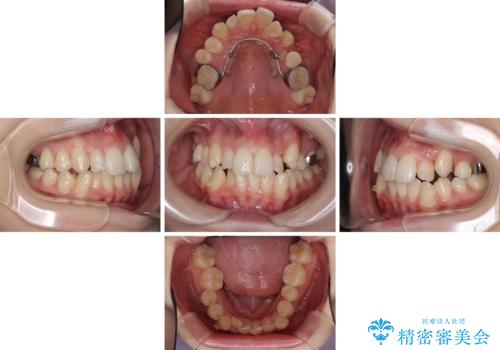

補助装置を併用したインビザラインでの八重歯の抜歯矯正

- 八重歯と奥歯の咬み合わせを気にして来院された患者様です。

インビザラインによる矯正治療を希望されたため、八重歯改善のための抜歯矯正部分は補助装置を併用し、その後はインビザラインにて行うこととしました。

下顎の右側変位が顕著であったため、ワイヤー矯正の方が咬み合わせは改善しやすいのですが、ある程度は時間がかかっても良いとのことであったので、インビザラインにて矯正治療を行うこととしました。

骨格的に下顎が右側に変位していたため、上下正中を合わせることは困難であることは分かっていました。それでも、なるべく合わせるようにとしたため、治療期間は長期間となりました。

長期間とはなりましたが、咬み合わせが改善され、患者様には大変満足していただきました。